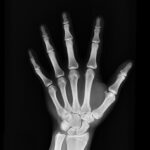

Waar is dit op gebaseerd? Uit de studie blijkt dat vegans over het algemeen een lager BMI hebben. Ook maken ze de 30% meer kans op botbreuken. Veganisten hebben vooral een grote kans op heupfracturen. En dit kan weer wijzen op minder sterke botten. Is dit een reden om veel zuivel te gaan consumeren? Nou nee. Allereerst hebben veganisten vanwege hun lagere BMI ook minder kans op welvaartsziekten, zoals hart- en vaatziekten. Hiernaast is het niet heel gek dat je sneller een bot breekt, als je minder lichaamsmassa hebt. Als je meer weegt, heb je namelijk een soort stootkussentje voor als je valt. Als je wat minder weegt, heb je dit stootkussentje niet.

Wat is de oplossing hiervoor? Zorgen dat je lekker beweegt! Door in beweging te blijven, bijvoorbeeld door lekker te wandelen, te fietsen of aan krachttraining te doen, werk je aan je spiermassa. Dit zorgt ervoor dat je een stootkussentje ontwikkeld. Hiernaast is het belangrijk om gevarieerd te eten. Veel groente, fruit, bonen, granen, zaden en pitten. Op deze manier kun je voldoende calcium, vitamine D en vitamine K2 binnenkrijgen, wat weer essentieel is voor gezonde botten.